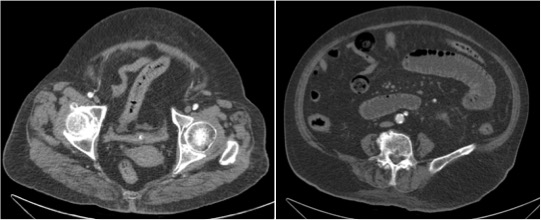

Se realiza TC de abdomen en vacío y con contraste en fase portal:

Estamos ante un cuadro de isquemia intestinal en un paciente con bajo gasto cardiaco con afectación principal de asas intestino delgado, territorio vacularizado por la arteria mesentérica superior.